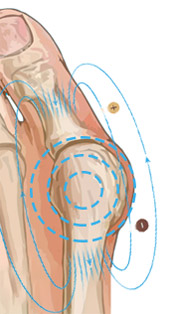

С целью устранения Hallus valgus (бурсита) и негативных симптомов, сопровождающих деформацию ступней, успешно применяется магнитотерапия. Магнитотерапия – уникальный метод физиотерапевтического лечения с помощью воздействия на организм постоянным, переменным или бегущим магнитным полем. Процедура является безопасной и не вызывает болезненных ощущений.

Чтобы купировать воспалительный процесс, достаточно использовать магнитную шину FootRelax ежедневно в течение 3-5 часов. Это способствует не только выравниванию фаланг пальцев и уменьшению деформации, но также благодаря воздействию магнитов происходит стимуляция нервных окончаний, повышается тонус тканей, улучшается кровообращение. FootRelax фиксирует большой палец в нужном положении, снижает нагрузку на ступни, купирует боль, облегчает ходьбу и возвращает здоровья ступням.